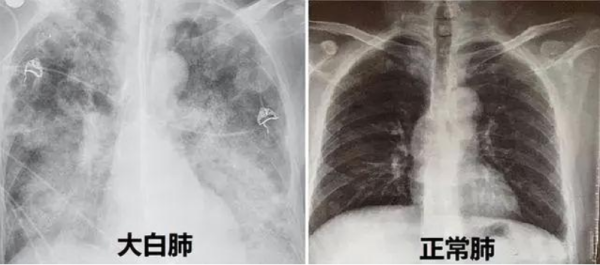

“患者入院时,我们给他做了详细的检查,发现老人的血氧饱和度只有70%,呼吸频率增快约30次/分,CT检查双肺呈现毛玻璃样影,病灶边缘模糊不清,双肺呈现‘白肺’状态,血气分析提示呼吸衰竭,病情十分危重。”香港马会app

)全科医学科主任、主任医师张辉容介绍,正常人的血氧饱和度通常在95%到100%之间,当下降到90%以下,人体可能因大脑氧气不足而出现昏睡,低于80%则可能对重要器官造成损害,甚至会直接导致窒息、休克、死亡等悲剧的发生。像张爷爷这种情况已经非常危急,幸好护士的电话随访给他争取了抢救治疗的时间,后续医护人员对老人进行了呼吸机辅助呼吸、俯卧位通气、抗感染、营养治疗、肺康复等综合救治,老人的病情开始好转,成功撤掉呼吸机,“白肺”开始吸收,血氧饱和度逐渐恢复到95%以上。

“CT影像检查显示白肺,说明肺炎病变范围较广,甚至几乎累及整个肺部,老人已经发生呼吸衰竭,严重时甚至会出现急性呼吸窘迫综合征。”张辉容主任介绍,肺部是由肺泡组成的,肺泡里边充满了空气,在CT检查时,它通常显示为灰黑色。由于感染、创伤各种原因导致的肺泡里出现炎症,或者感染有渗出液时,肺泡就被这些渗出液或者炎性细胞所填充,有很多沉积物、甚至实变,肺部透过X线的能力大幅减弱,在胸片或者CT上,会看到肺的整个组织不是灰黑色,而是白色,就是大家通常说的“白肺”,这类情况死亡率较高。但白肺是可以预警的,及时发现缺氧状况,及时救治是关键。